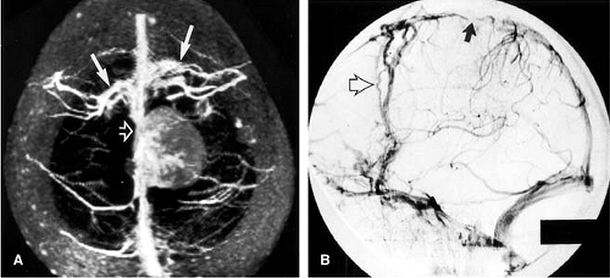

Chụp cộng hưởng từ hệ mạch máu nội sọ tiêm thuốc đối quang từ là kỹ thuật sử dụng từ trường và các xung năng lượng sóng vô tuyến đồng thời sử dụng thuốc đối quang từ đường tĩnh mạch nhằm mục đích khảo sát hệ mạch cảnh - sống nền nội sọ hiệu quả. Phương pháp này cho phép thăm khám cả hệ động mạch và hệ tĩnh mạch não, có khả năng phát hiện được nhiều bệnh lý mạch máu não như hẹp mạch, dị dạng động tĩnh mạch, phình mạch, dị dạng tĩnh mạch Não hay các huyết khối động mạch cũng như tĩnh mạch.

Kỹ thuật này là 1 kỹ thuật khảo sát hệ mạch cảnh sống nền và nội sọ hiệu quả, độ chính xác cao hơn so với thăm khám hệ mạch máu não bằng cộng hưởng từ không tiêm thuốc đối quang từ. Tuy nhiên có thể xảy ra các tai biến liên quan đến thuốc đối quang từ.

- Bác sĩ nghi ngờ bệnh nhân mắc các bệnh lý mạch máu nội sọ như:: dị dạng mạch máu não (động mạch hoặc tĩnh mạch), chứng phình động mạch, hẹp mạch não trong và ngoài sọ;

- Đột quỵ não: Nhồi máu não tìm vị trí tắc mạch lớn, Xuất huyết não mà cần tìm phình mạch, dị dạng mạch, dò động mạch cảnh - xoang hang...;